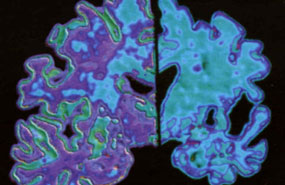

El Alzheimer -según los especialistas- surge por la acumulación en el cerebro de un fragmento proteico llamado beta-proteína que se agrega generando depósitos insolubles. (GRAFICO)

El Alzheimer -según los especialistas- surge por la acumulación en el cerebro de un fragmento proteico llamado beta-proteína que se agrega generando depósitos insolubles, las llamadas placas amiloides.